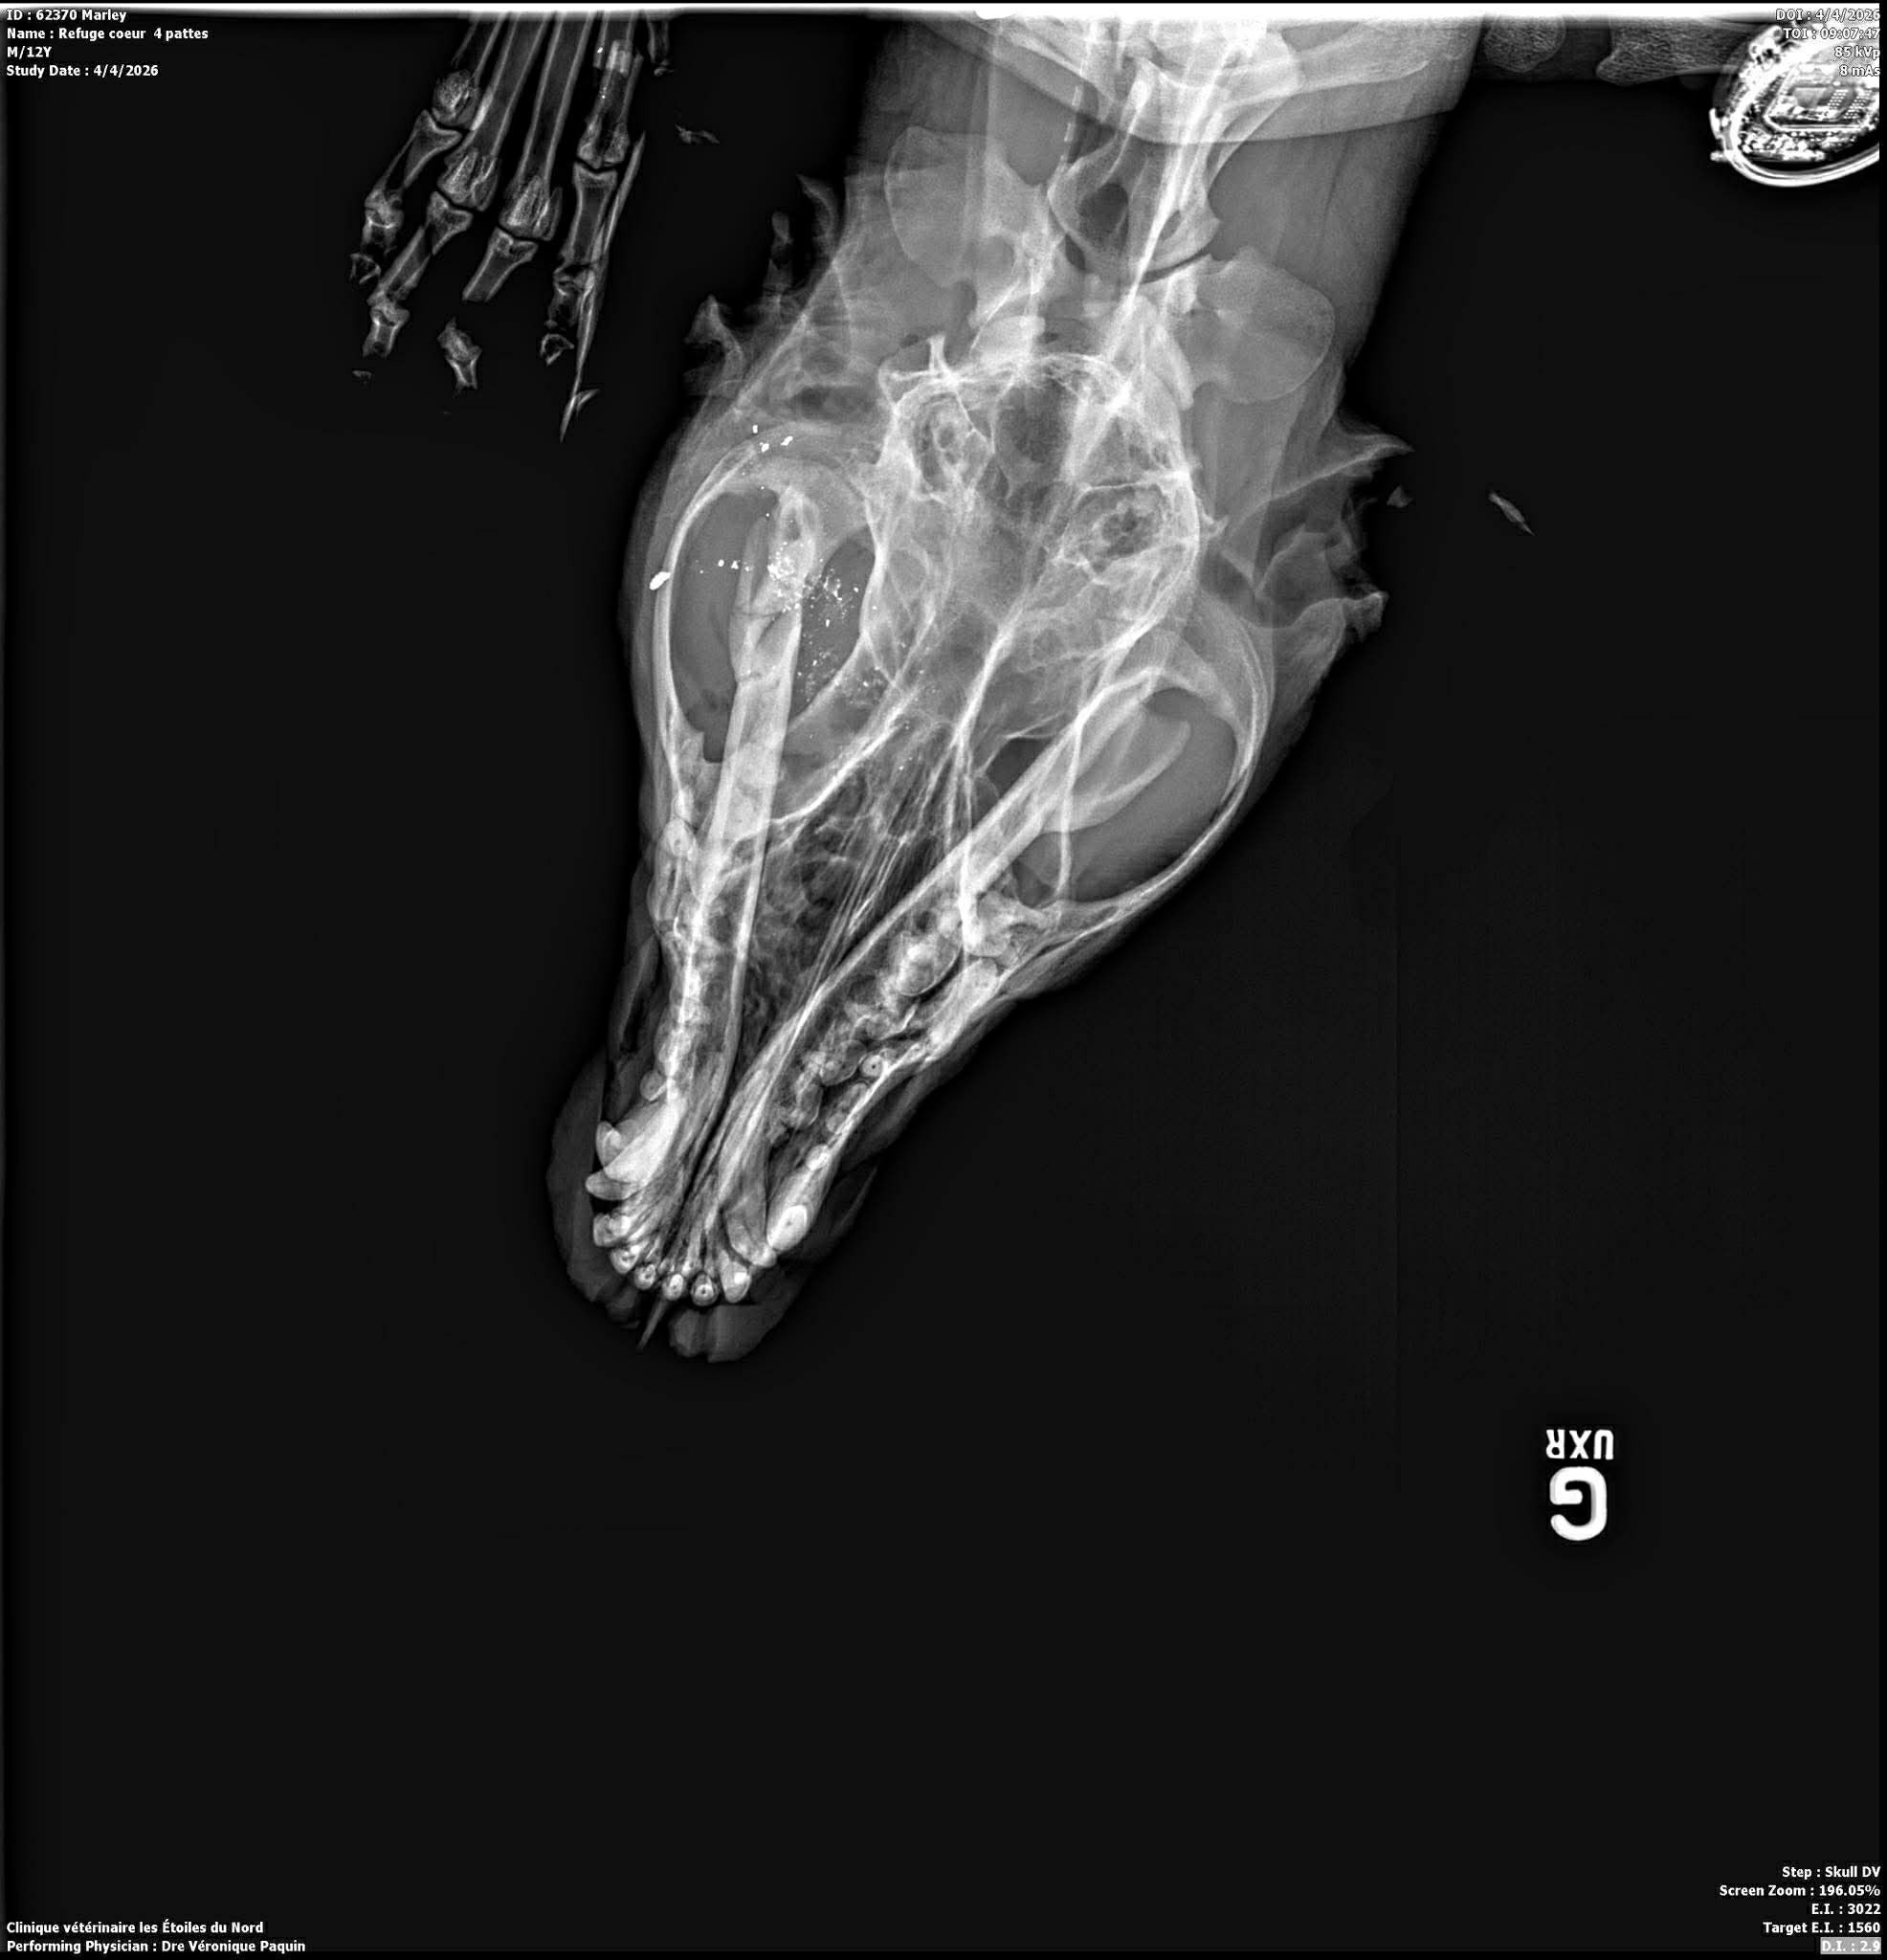

Nous pouvons maintenant vous donner plus de détails. Pongo a subi un traumatisme par projectiles d’arme à feu avec des lésions à la joue droite, à l'oeil droit et à l'intérieur de la gueule (gencives, palais et palais mou). Il a aussi une plaie par balle à une de ses pattes avec fracture du premier métacarpe.

Pongo est hors de danger et espérons que sa réhabilitation ira bien. Changement des pansements à la patte tous les jours pour une semaine et médicaments pour 2 semaines et beaucoup de repos. Il va sans dire que des suivis rigoureux seront nécessaires.